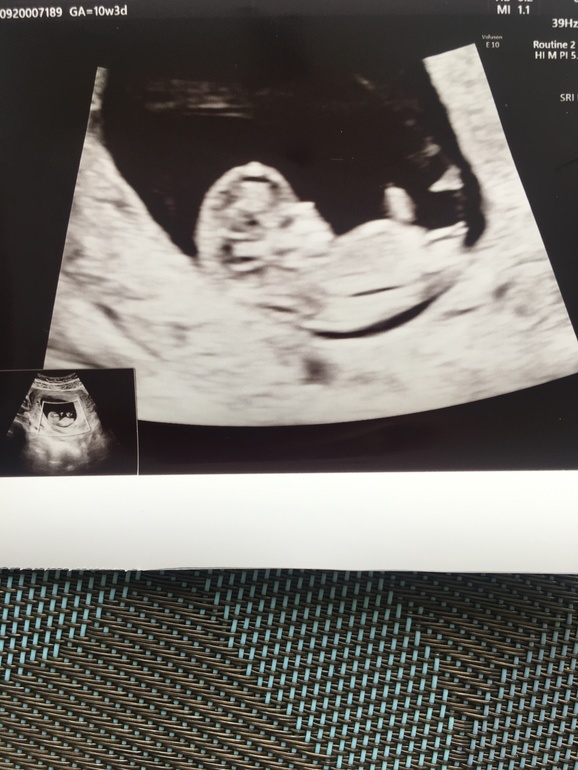

Но у нас все хорошо!!!) малыш подрос, ктр 4 см, опережает на 4 дня, чсс 164/мин.Уже помахал нам ручками и ножками, от чего муж был в шоке)

Ну и фото на память)